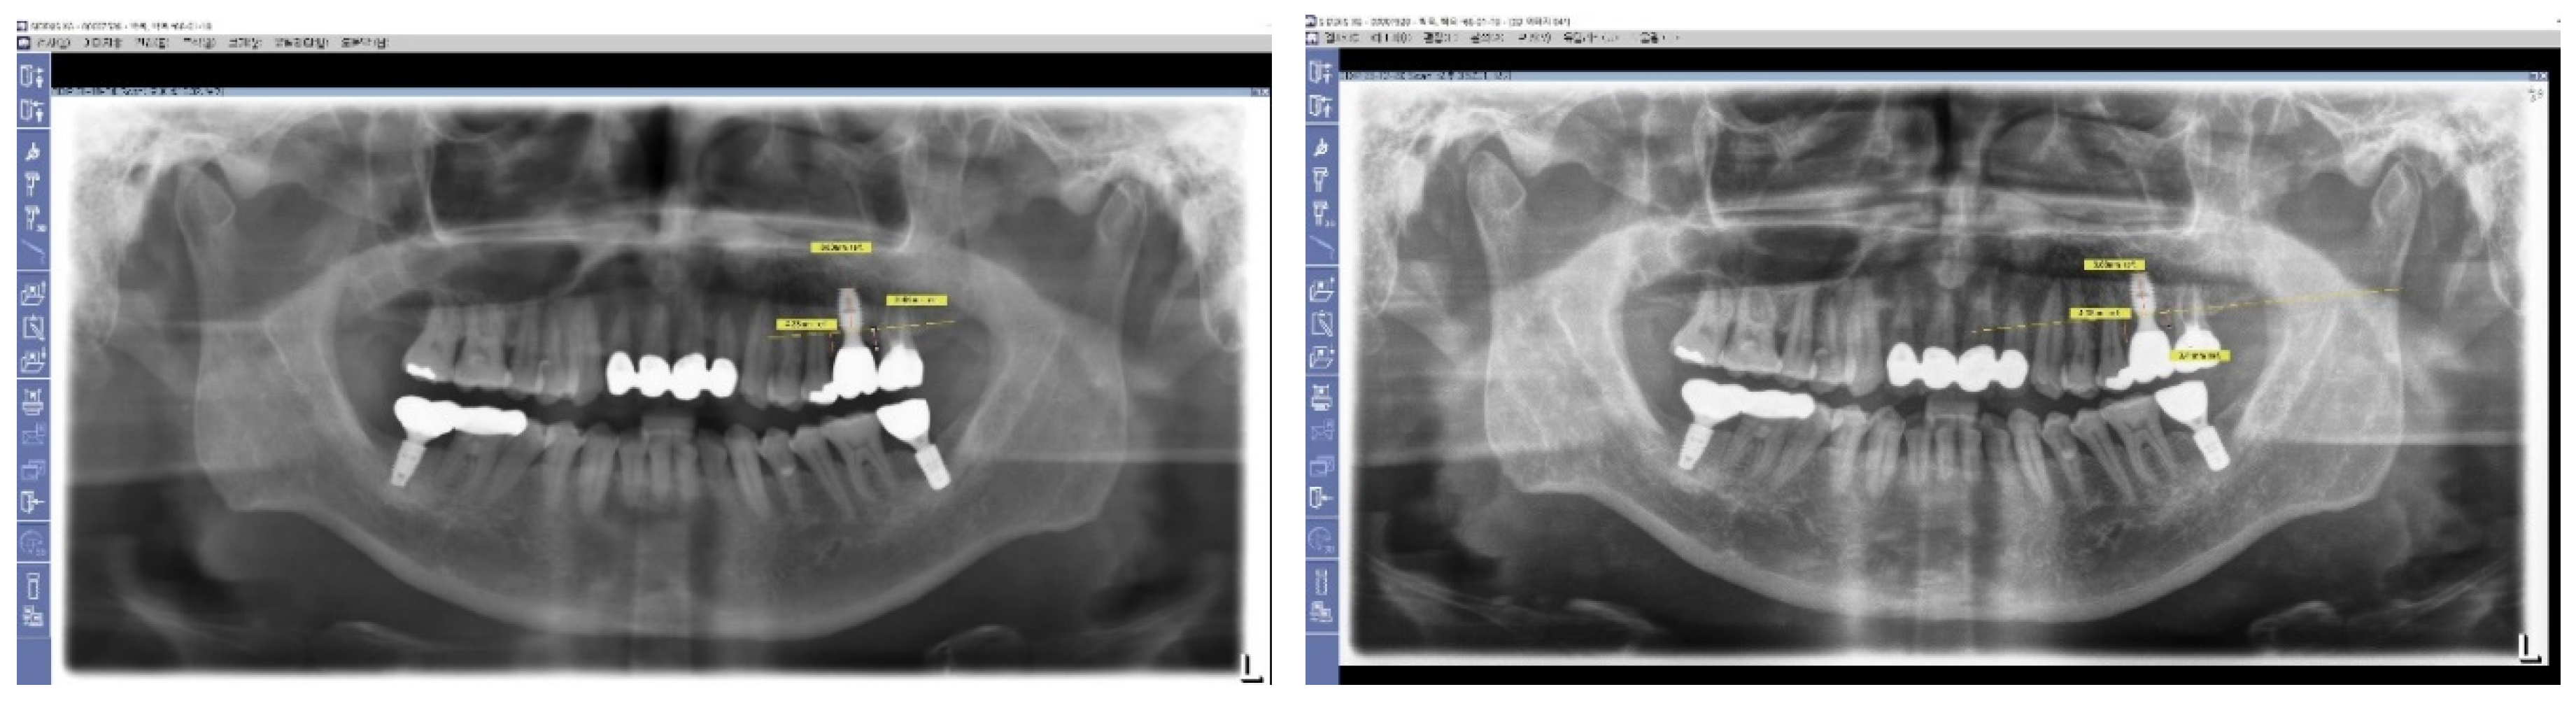

Figure 7. Long-Term Stability of Lower First Implants. This figure displays a panoramic view X-ray taken in 2023, showing the stable results of both lower first implants that were placed in 2012. These implants, which utilize Subcrestally Placed Implants (SPI) with Internal Platform Switching (IPS) design (specifically Bicon implants), demonstrate long-term stability and successful integration.